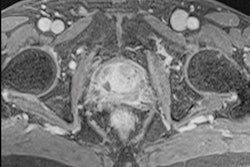

Researchers from Bordeaux, France, say there's a strong need for additional data about the use of breast MRI in this indication. They evaluated the accuracy of breast MRI in identifying lesions requiring excision for patients who had experienced suspicious nipple discharge but had normal mammograms and ultrasound scans. Their results, analysis, and clinical images are worth a look.